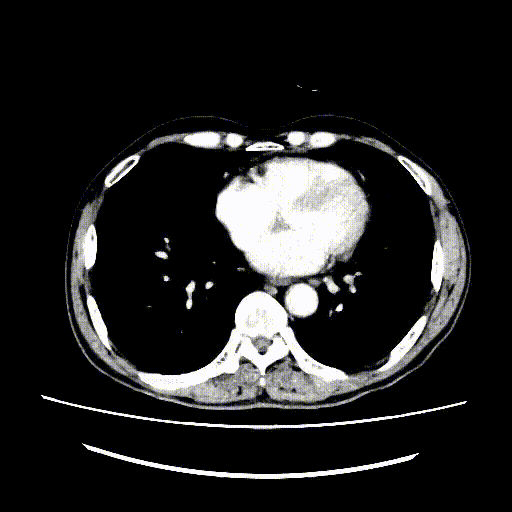

图为:术后1月腹部CT及增强扫描